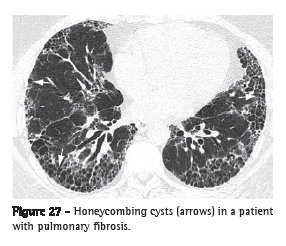

Honeycombing, or honeycomb lung (faveolamento, or favo de mel)

Honeycombing is characterized by pulmonary cysts created as a result of the destruction of the distal air spaces due to parenchymal fibrosis, with loss of acinar and bronchiolar architecture. Honeycombing cysts are covered with metaplastic bronchiolar epithelium and represent the end stage of a number of pulmonary diseases.(1,48) On HRCT scans, honeycombing is characterized by multiple cysts, generally subpleural and of comparable diameters (typically 0.3-1 cm), grouped on layers and sharing well-defined walls of 1-3 mm in thickness (Figure 27).(49)

Honeycombing is a tomographic marker of pulmonary fibrosis. The principal causes of honeycombing include idiopathic pulmonary fibrosis, collagenoses, chronic hypersensitivity pneumonitis, drug-induced pulmonary reactions and asbestosis.(28) It should be differentiated from paraseptal emphysema and traction bronchiolectasis.